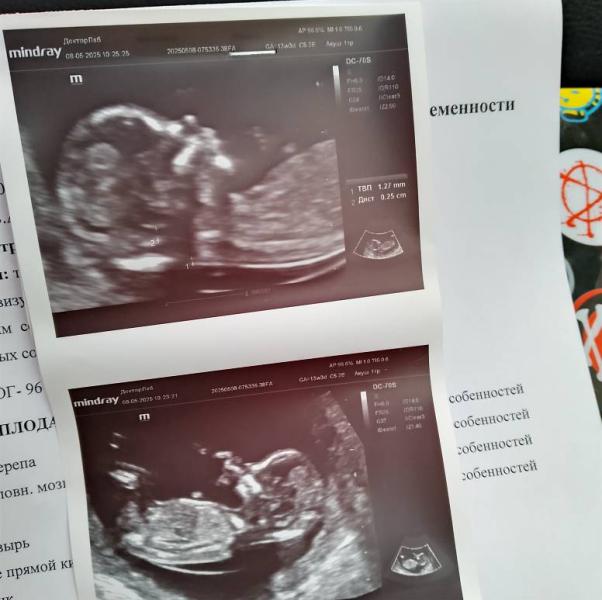

Долгожданная принцесса в животике 🌺 до сих пор не верю🙈 сейчас главное, чтобы у леди не выросла пипка 😅

Тоже сегодня не было письки на скрининге 😁 начиталась, что она бы уже была, но не факт.

Я у Исхакова была, говорят он в этом плане мастер вроде 😁 ну он убедительно сказал, что это девочка 😁 проверим на втором скрининге